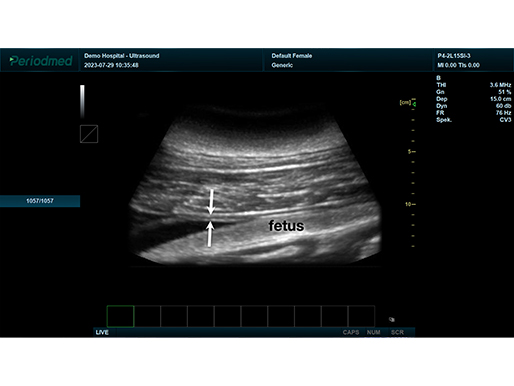

B模式 怀孕 牛

线阵探头-B模式-怀孕 牛